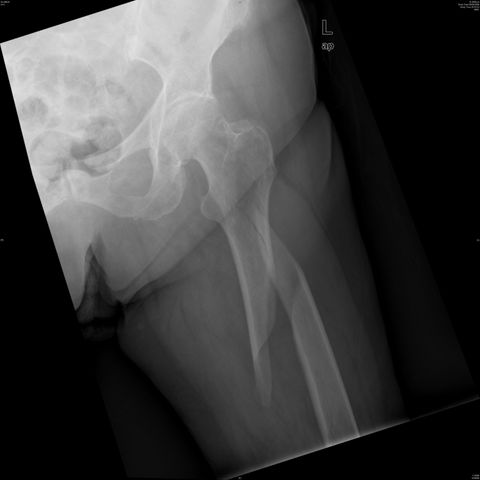

Fractura intertrocantérea de fémur, osteosíntesis

Fractura de fémur, osteosíntesis

osteosíntesis fractura fémur